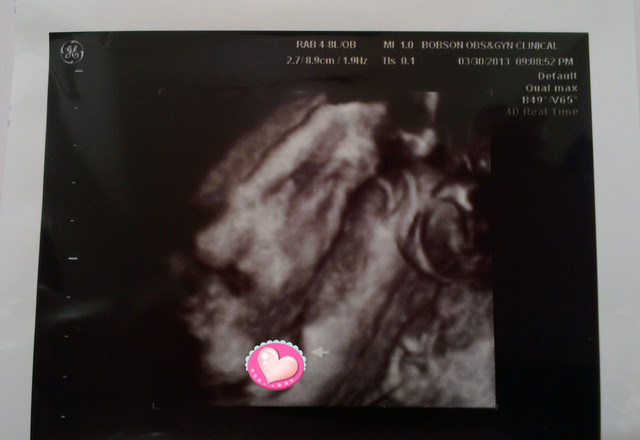

看看一開始產檢醫生幫我拍的照片

章魚妹妹在打呵欠啊

嘴巴張這麼大

還是最後笑起來的比較可愛

醫生說章魚妹已經足月

所以隨時要生都可以

不用擔心早產的問題

章魚妹

頭圍:

8.58 cm

肚圍:

32.44 cm

加起來重量為

2826g